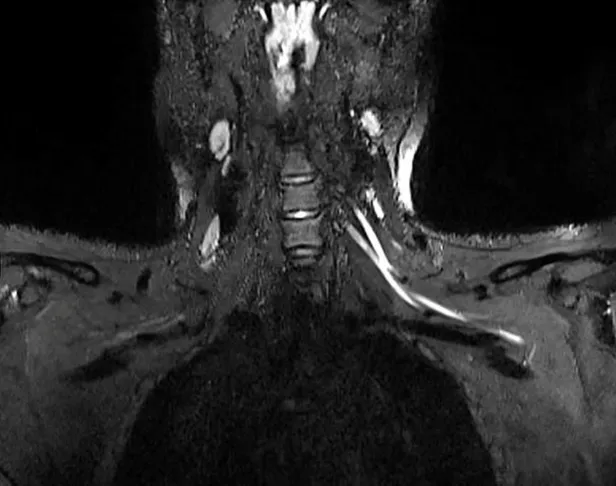

Son dakika haberi! Bilim insanları uzun süreli yeni tip koronavirüs (Kovid-19) hastalarında görülen yorgunluk ve ağrının sebebini ilk kez ortaya koydu. ABD’de yer alan Northwestern Üniversitesi’nden araştırmacılar MRI ve ultrason tekniklerini birleştirerek, geleneksel yöntemlerle tespit edilemeyen Covid-19'un sinir sisteminde yarattığı hasarı kanıtladı. Geliştirilen yeni teknolojinin doktorlara, hastaları için uygun tedavi yöntemini belirlemesini sağlayarak hayat kurtarabileceği belirtildi.

NTV'nin haberine göre, Radiology dergisinde yayımlanan çalışmanın başyazarı Doktor Swati Deshmukh, konuya ilişkin yaptığı açıklamada, "Ağrı boynunuzdaki, dirseğinizdeki veya bileğinizdeki sorunlardan kaynaklanıyor olabilir ve bunu anlamanın en iyi yolu MRI veya ultrasondur.

Yaptığımız çalışmayla çok küçük sinirleri bile gösteren gelişmiş görüntüleme sunuyoruz. Bu da sorunun nerede olduğunu tespit etmemize, ciddiyetini değerlendirmemize ve buna neyin neden olabileceğini önermemize yardımcı oluyor" ifadelerini kullandı.

Bununla birlikte Doktor Deshmukh, corona virüsün aşırı bağışıklık tepkisini tetiklemesinden dolayı, vücut tarafından üretilen antikorların sadece enfekte hücrelere değil, sağlıklı dokulara da saldırmaya zorlayarak ciddi semptomlara neden olduğunu söyledi. Bilim insanı, olayın ardından sinir sisteminde de şiddetli iltihaplanma görülebileceğini açıkladı.

Doktor Deshmukh, "Ciddi Covid-19 vakalarında vücudun bağışıklık tepkisinin akciğerlere saldırmasına benzer bir şekilde, bazı hastaların bağışıklık tepkisi sinir sistemini etkileyebilir" dedi.